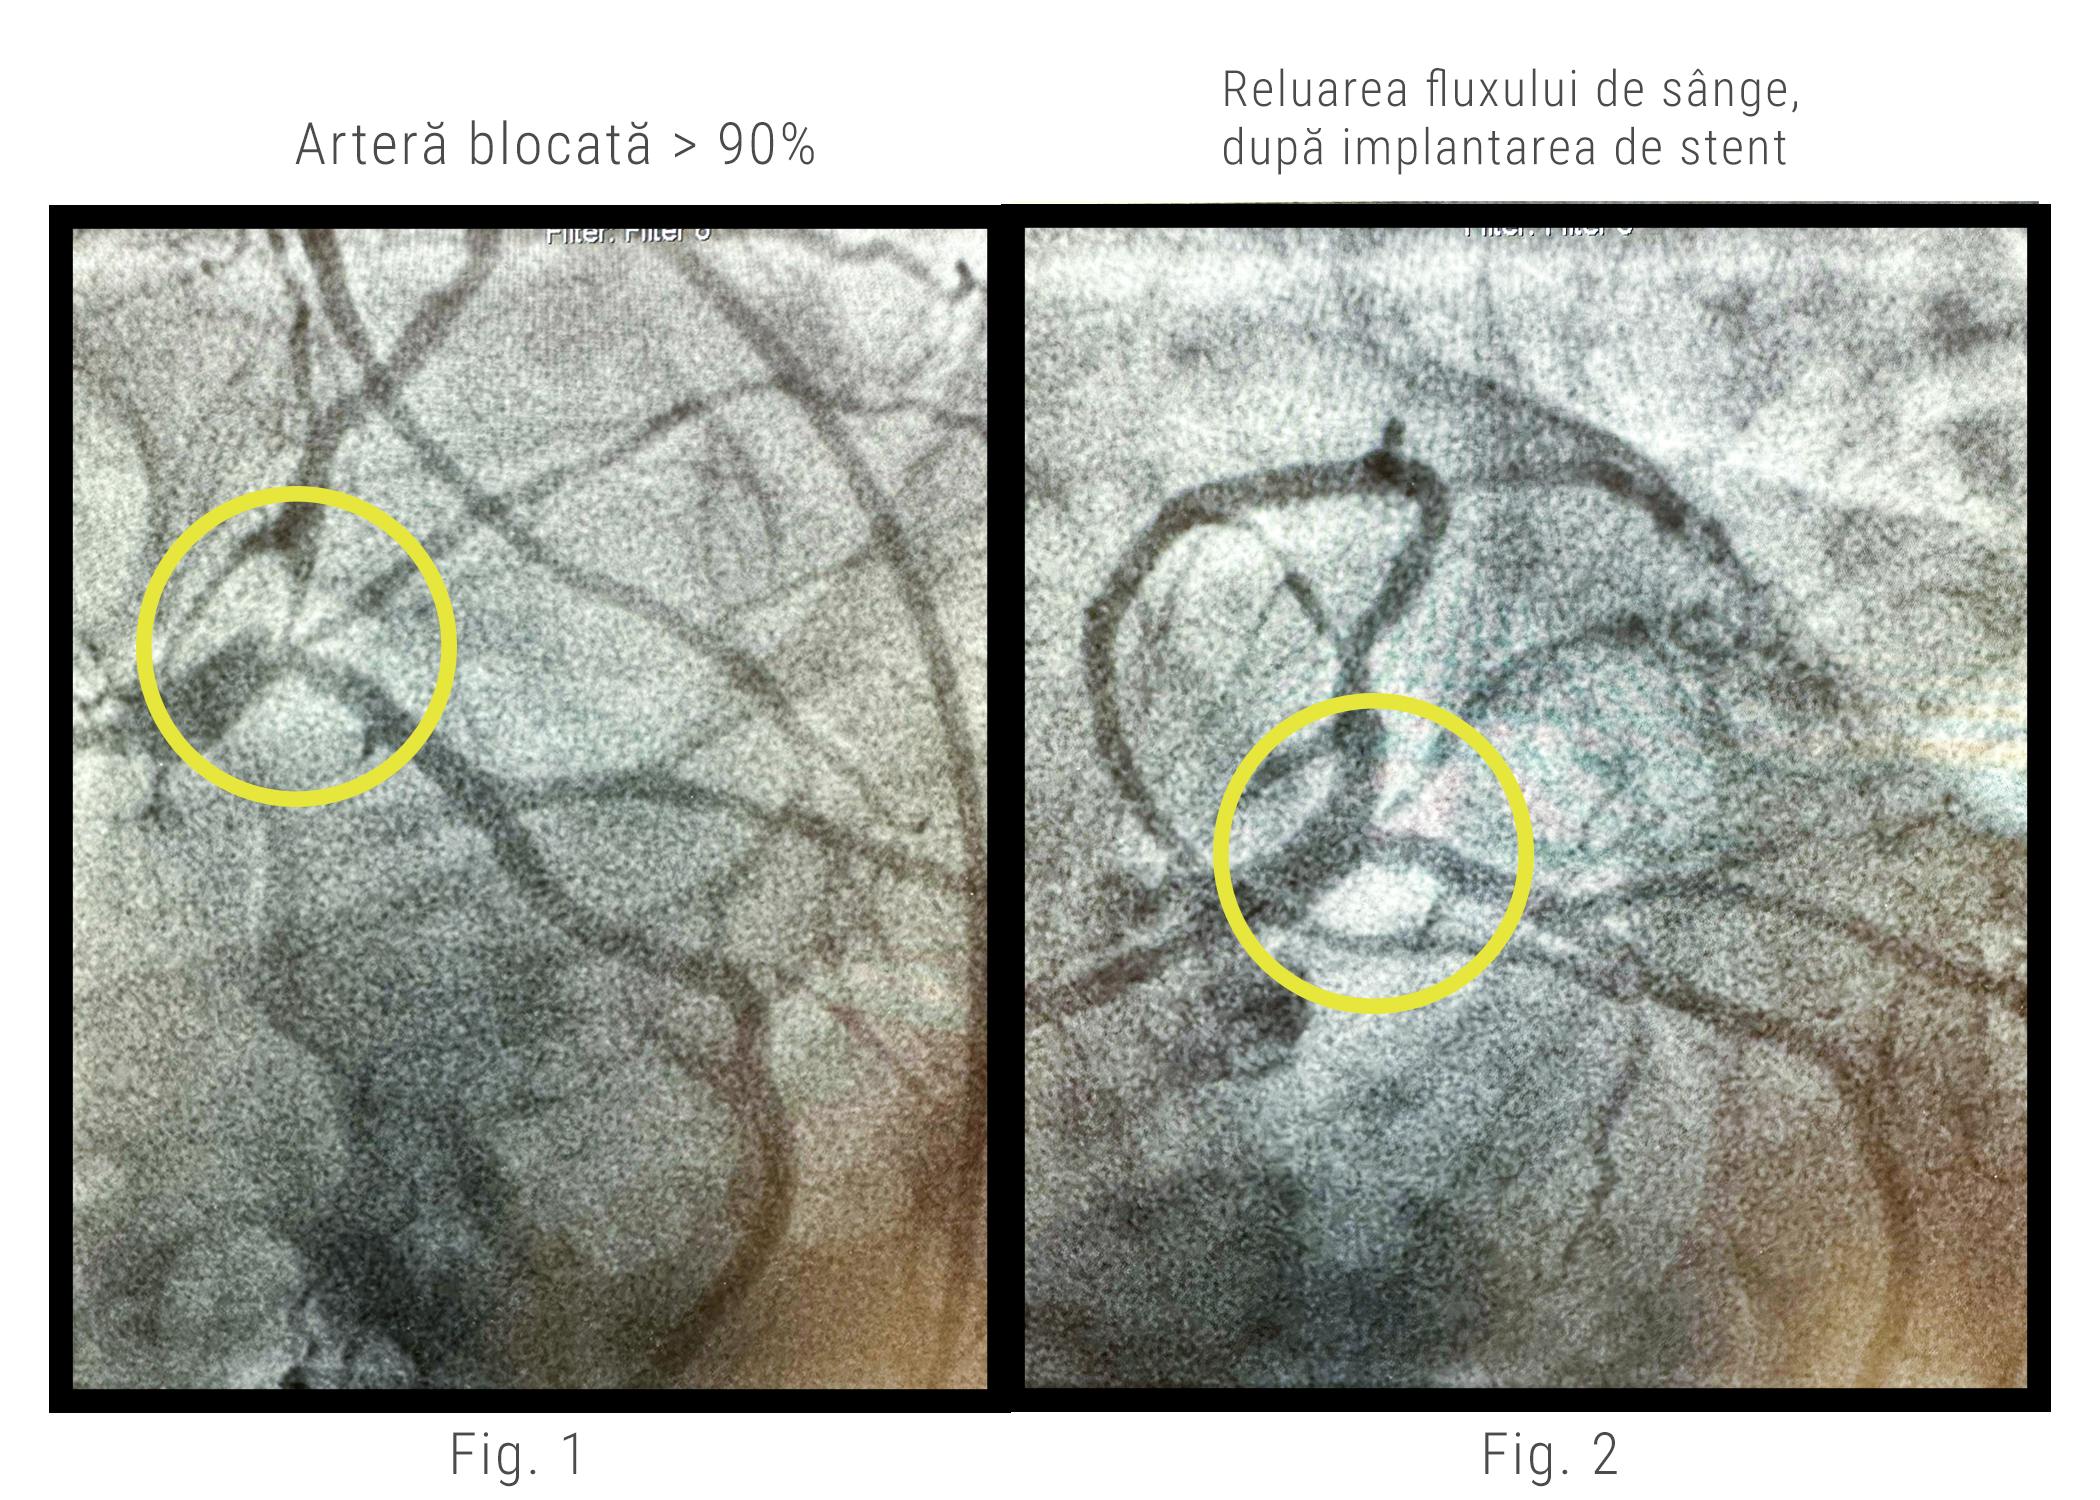

În cazul pacientului nostru care manifesta dureri toracice, dr. Adnan Mustafa a efectuat coronarografia care a evidențiat prezența unei stenoze critice pe artera descendentă anterioară - ADA (cea mai importantă arteră care alimentează inima).

Depunerea de grăsime îngusta vasul de sânge în proporție de peste 90%, de la originea arterei, cu aspect de placă în contracurent la nivelul trunchiului coronarian stâng, în segmentul distal. (Fig. 1)

În astfel de cazuri, este deosebit de important ca medicul cardiolog intervenționist să intervină imediat și să trateze vasul de sânge blocat. Altfel pacientul riscă să sufere în orice moment, un blocaj total al arterei ceea ce înseamnă un infarct miocardic, eveniment care îi pune viața în pericol.

Ca și în timpul coronarografiei, medicul intervenționist introduce un cateter special, predispus cu balon și stent. Odată ce a ajuns în dreptul îngustării, medicul umflă balonașul care, la rândul lui, va expanda stentul. În timp ce stentul coronarian este expandat, depunerea de grăsime este aplatizată de pereții arterei și astfel, circulația sângelui este reluată. (Fig 2)